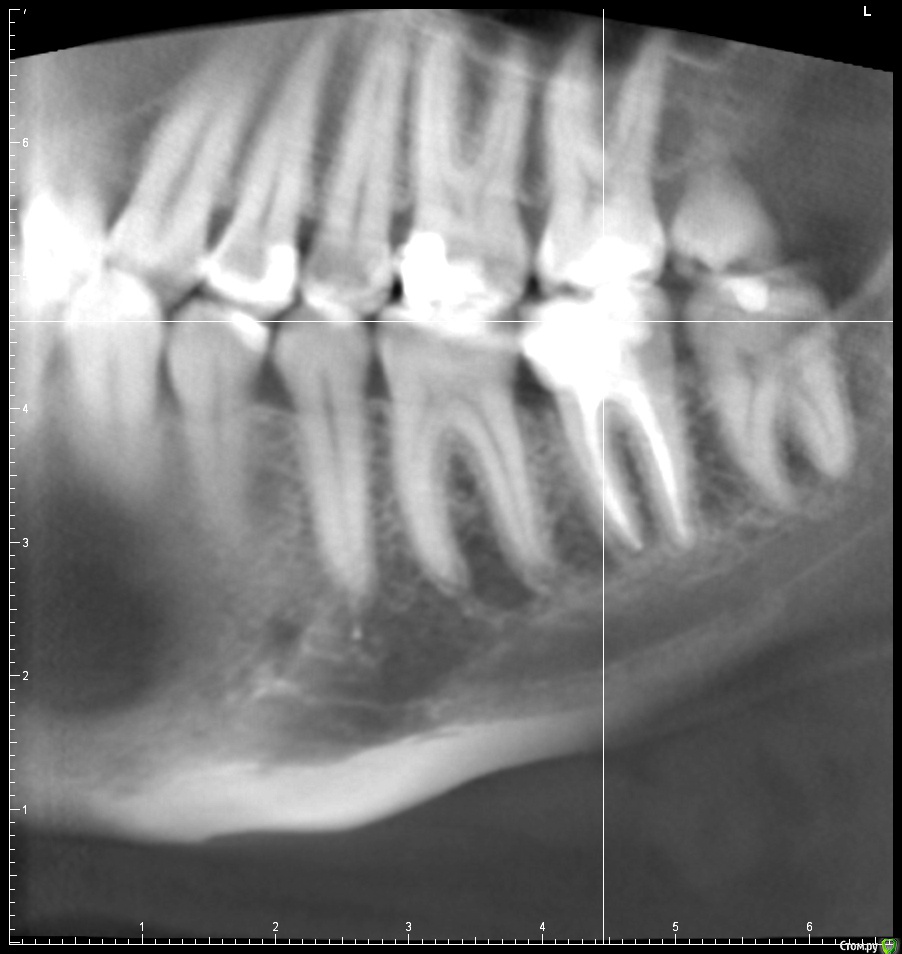

В августе прошлого года у меня начал сильно болеть десны и зуб на фоне обострения поллиноза. Врач обнаружил пульпит в болевшем зубе и еще несколько очагов кариеса по КТ. Очаги кариеса были запломбированы, в пульпитом 37 зубе было проведено депульпирование и пломбировка каналов. При пломбировке каналов врач что-то прижигал нагретой палочкой, раньше я думал, что при пломбировке использовалась гуттаперча. После лечения ощущались боли при надкусывании в 36 зубе несколько недель, на которые я не обращал внимания.

Прикладываю срезы с КТ от начала января 2017, скан распечатки прицельного снимка 36 37 зуба от ноября 2016.